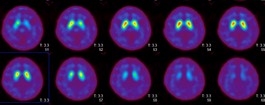

脳血流シンチグラム([123I ]IMP)

レビー小体型認知症  後頭葉優位の血流低下